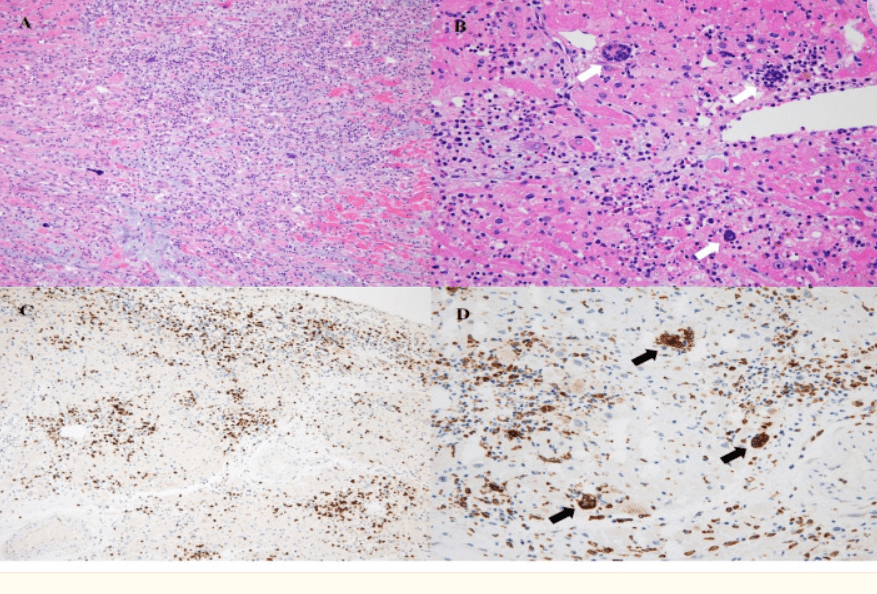

Ici des syncytia visibles dans les pneumocytes de personnes décédées du COVID

elifesciences.org/articles/65962…

Elément de réponse: le coeur de cette dame de 42 ans n’a pas résisté 4j après sa 2ème dose de Pfizer. On a dû lui greffer un nouveau coeur … myocardite fulminante à cellules géantes! Dommage, pas à risque de COVID!

Fulminant Giant Cell Myocarditis following Heterologous Vaccination of ChAdOx1 nCoV-19 and Pfizer-BioNTech COVID-19A 48-year-old female patient underwent a heart transplantation for acute fulminant myocarditis, following heterologous vaccination with the ChAdOx1 nCoV-19 and Pfizer-BioNTech COVID-19. She had no his…https://www.ncbi.nlm.nih.gov/pmc/articles/PMC8950462/

L’histopathologie montre la nécrose (mort des cardiomyocytes), une forte infiltration de macrophages, lymphocytes T, quelques éosinophiles et surprise des cellules géantes d’origine monocytaire (CD68+) … mais d’où viennent-elles et que deviennent-elles?